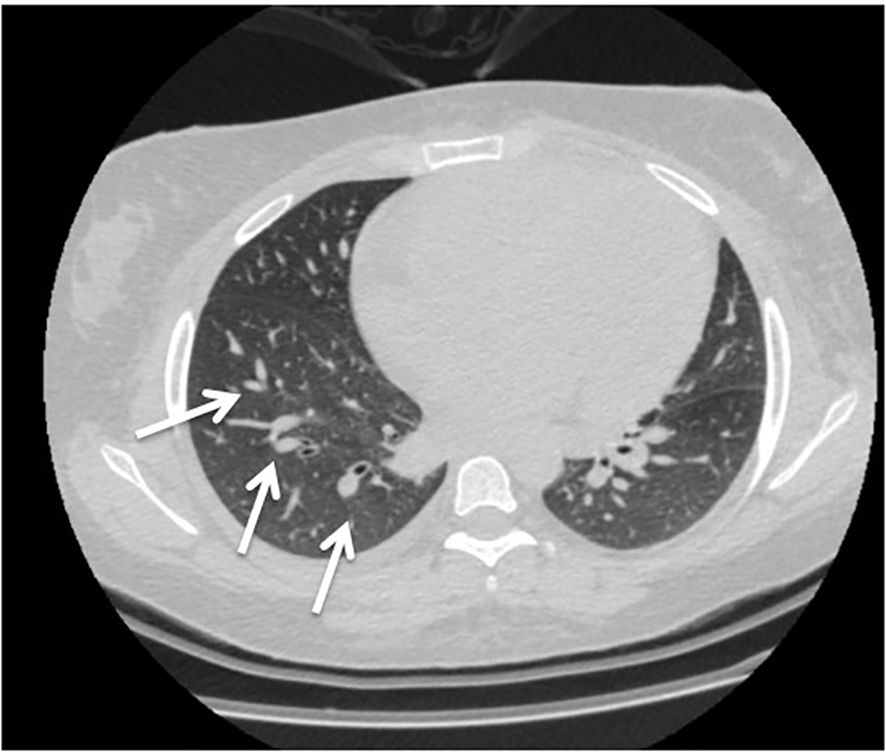

Two weeks after cyclophosphamide therapy, the patient presented to our department with complaints of watery diarrhea, vomiting, hematochezia, shortness of breath, and general weakness. Upon examination, the patient appeared ill and pale. Her blood pressure was 190/85 mmHg, her heart rate was 85 beats per minute, her oxygen saturation (SpO₂) was 96%, respiratory rate was 19 breaths/min, and temperature was 37.9 °C. A respiratory examination revealed decreased air entry and basal crepitations. Grade 4 bilateral lower limb pitting edema was observed. Results of laboratory tests performed at admission revealed anemia, high neutrophils with low leukocytes, lymphopenia, and elevated creatinine, which was her usual baseline; otherwise, the results were normal (Table 1). Hemolytic anemia was confirmed by blood smear examination. Subsequent Computed tomography (CT) revealed bilateral mild pleural effusion and nodular consolidation in the lower right lobe encircled by ground-glass opacities. The patient was admitted for further assessment and treatment. (Figure 1). Echocardiography revealed mild left ventricular and left atrial dilatation.

Figure 1. Computed tomography (CT) revealed bilateral mild pleural effusion and nodular consolidation in the lower right lobe encircled by ground-glass opacities (white arrow). She was admitted for additional assessment and treatment.